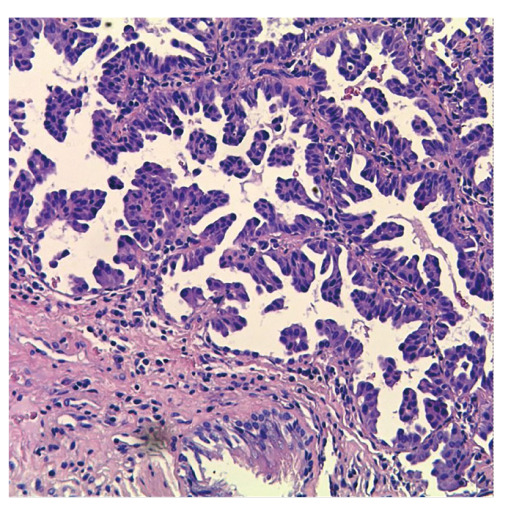

Abstract Image